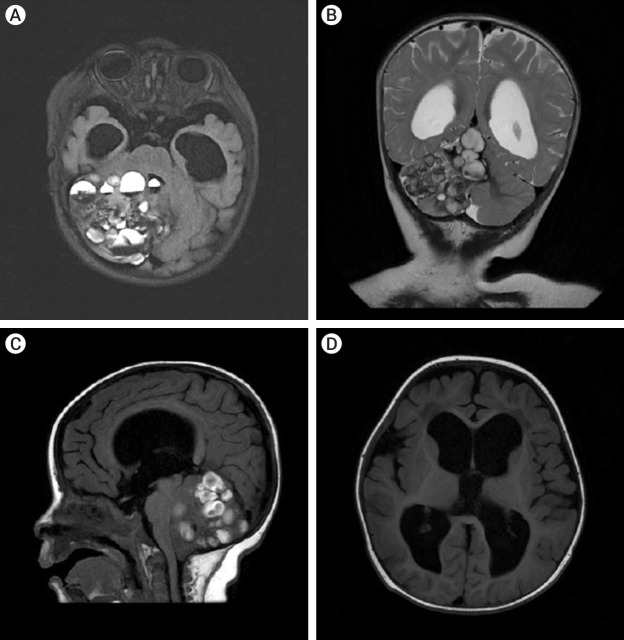

儿童巨大小脑海绵状瘤非常罕见,必须与出血性小脑肿瘤区分开来。巨型小脑海绵状瘤的诊断和治疗具有挑战性,但完全的手术切除可带来良好的结果,大多数病例的神经功能可完全恢复。我们报告了一例八个月大的婴儿,他被诊断出患有巨大海绵状瘤,导致继发性梗阻性脑积水,并伴有神经精神症状。患者接受了枕骨下入路的副颅骨开颅手术,完全切除了海绵瘤。经过九个月的观察,患儿的行走能力有所改善,神经系统也完全康复。我们还进行了文献综述,确定了包括本病例在内的 11 例儿童巨大小脑海绵状瘤病例。我们对这些数据进行了分析,以确定儿童巨大小脑海绵状瘤的临床特征、治疗方法和结果。

Giant cerebellar cavernomas in children are rare and must be differentiated from hemorrhagic cerebellar tumors. The diagnosis and treatment of giant cerebellar cavernomas is challenging, but complete surgical resection can lead to favorable outcomes and complete neurological recovery in most cases. We present a case of eight months old baby who was diagnosed with a giant cavernoma resulting in secondary obstructive hydrocephalus with neuropsychiatric presentations. The patient underwent a paramedian craniotomy surgery with a suboccipital approach and complete surgical resection of the cavernoma was done. Over nine months of observation, the child showed improvement in their ability to walk and fully recovered from a neurological perspective. We also conducted a literature review to identify eleven cases of giant cerebellar cavernomas in children, including our case. The data were analyzed to determine the clinical features, treatment, and outcomes of giant cerebellar cavernomas in children.